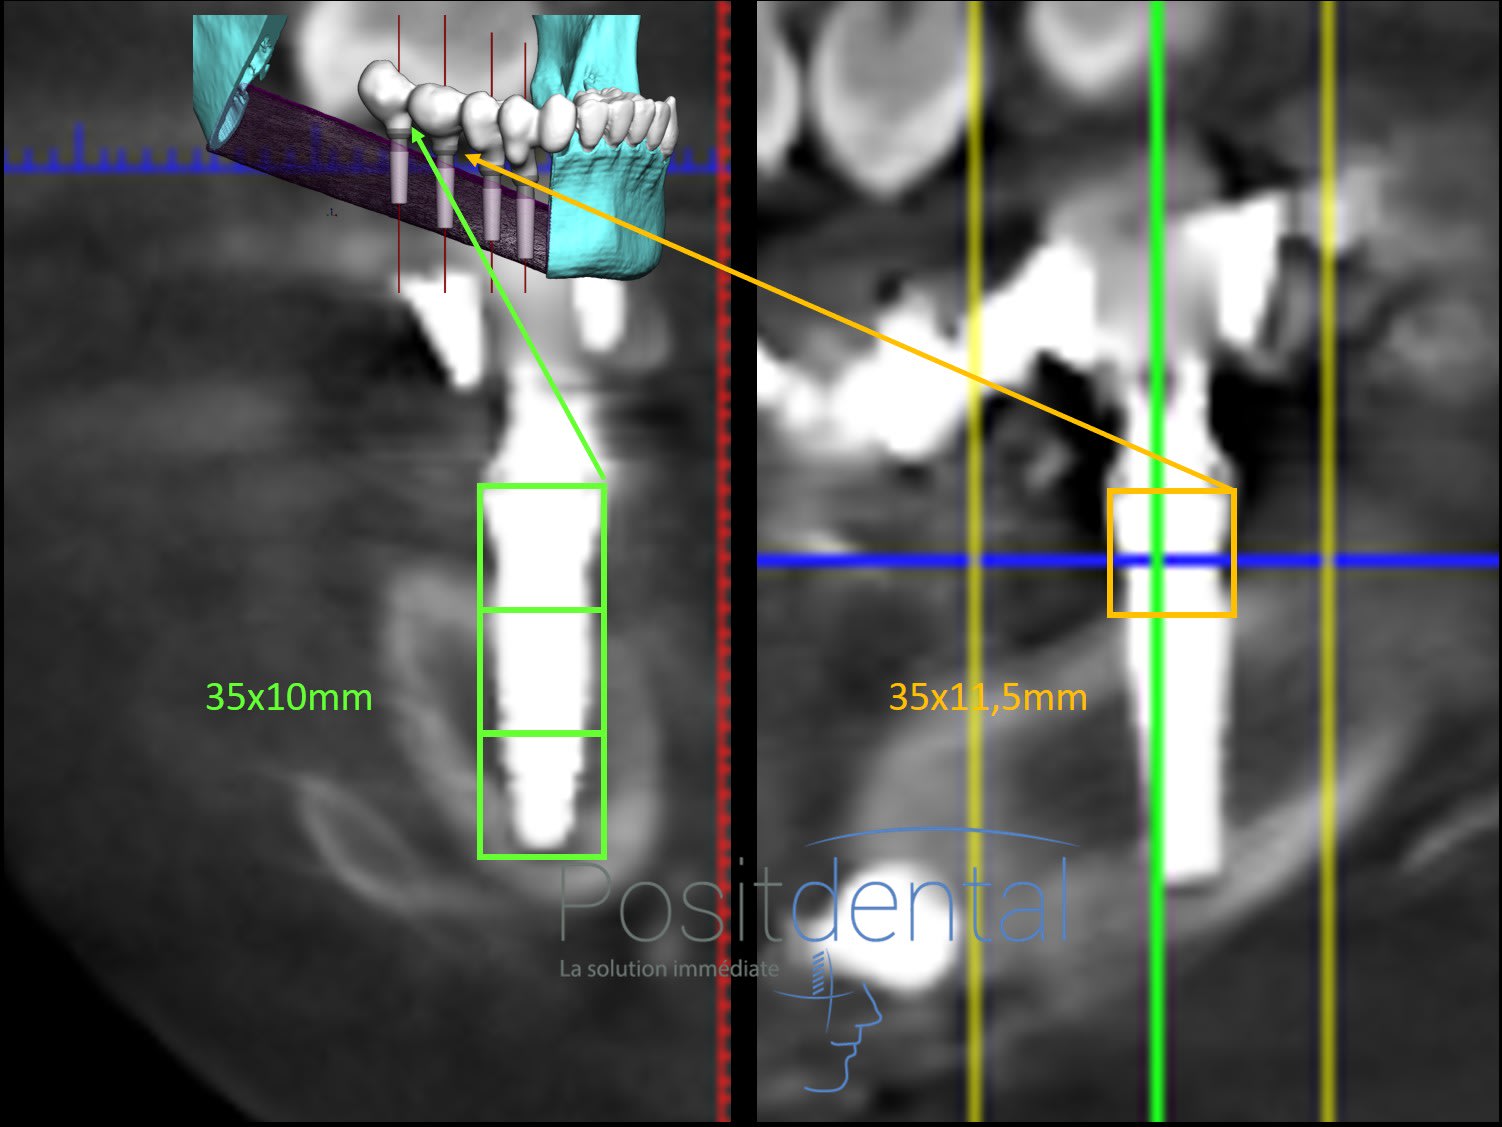

Pourquoi sur la coupe scaner ce trait ne forme pas un carré avec le MU?

Parce que tes histoires de carré n'ont aucun sens.

Regarde bien ta coupe, compare avec l'image de l'implant et tire les bonnes conclusions.

Tu vois le rétrécissement au niveau de la connection ? Je l'ai marqué avec des flèches rouges. Le col il est là et nulle part ailleurs

Ce qui n'a pas de sens et de refuser une methode qui donne une cote prècise pour controler le niveau du col de l implant

> une methode qui donne une cote prècise

lol... précise ?? si le trait rouge fait 4.5mm ton implant fait 7.8mm-8mm au max au lieu de 10mm.

c'est pas tres beau de piper autant son iconographie... surtout que ca trompe personne.

Fait des carré pour être précis